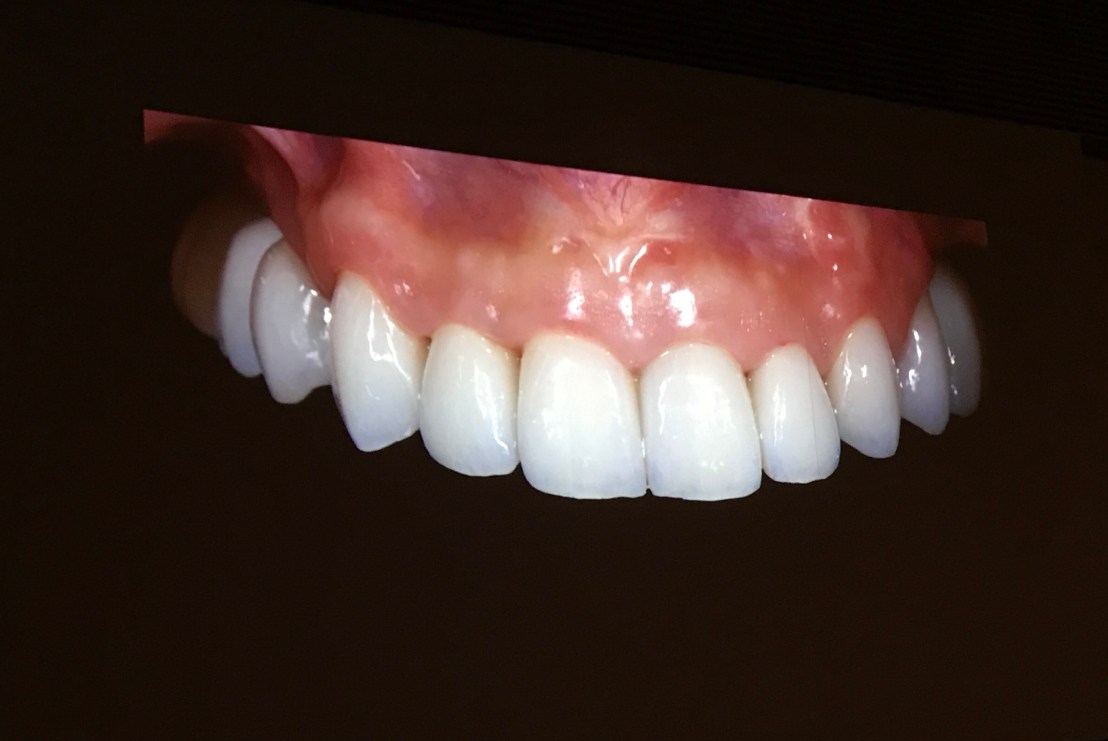

Final prosthesis

รูป 3 step ก่อน/หลังถอด Ortho/Final pros

แล้วส่งข้อมูลไปกลึงชิ้นงาน จนเป็น Final pros fix ในปากครับ